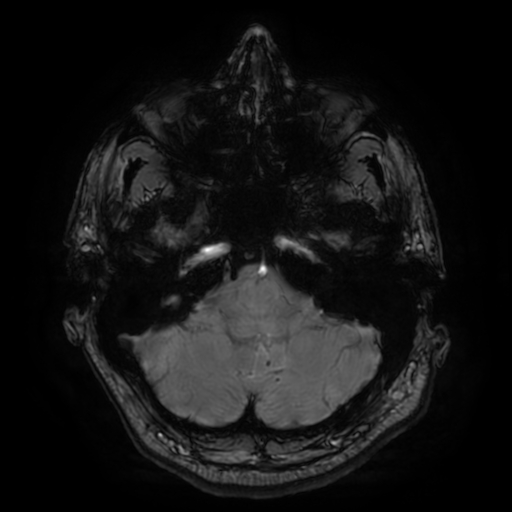

SEQUELAS DE TCE MODERADO-GRAVE — LAD GRAU II COM GLIOSE PONTINA E ATROFIA CEREBRAL PÓS-TRAUMÁTICA

• lesionBrain detectou 7 lesões visíveis em FLAIR (0.2472 cm³), sendo 6 juxtacorticais

• Compatível com: Microbleeds identificados nas imagens SWI + LAD Grau II + Gliose pontina

• CERES: Lobules IV direito e V bilaterais anormais

• Pode estar relacionado com gliose pontina (conexão ponte-cerebelo)

• lesionBrain: 6/7 lesões são juxtacorticais (regiões superiores)

• Padrão consistente com LAD Grau II: lesões juxtacorticais + tronco cerebral